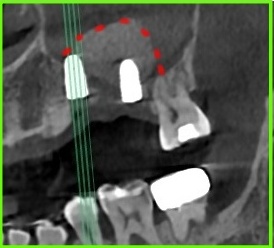

사진 1) 염증이 심한 치아를 발치하고 임플란트를 심어야 하는 상황이었습니다. 연두색 그림처럼 임플란트를 심어야 하는 상황이었죠.

사진 2) 발치를 한 뒤 한참을 기다려도, 염증이 심했던 자리에는 뼈가 차오르지 않습니다. 빨간색 실선만큼의 공간이 그대로 남아 있는 것이죠.

사진 3) 그림과 같이 뼈이식을 계획했습니다.(노란색 빗금 부위에 뼈이식)

사진 1) 잇몸뼈가 수직적으로 너무 얇은 상태입니다.(하얀색 실선)

사진 2) 임플란트를 식립하려면(초록색 네모), 상악동 거상술을 통해 뼈를 만들어 줘야 합니다.(노란색 실선)

사진 3) 실제 임플란트를 식립하고 상악동 거상술 뼈이식을 완료한 상태입니다.(빨간색 점선)